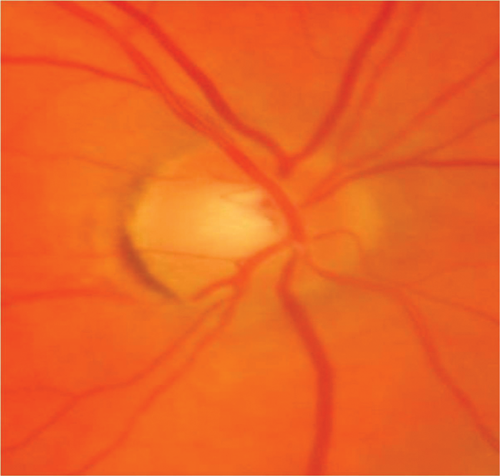

Case 4

A 21-year-old Asian man presented with bilateral, painful visual reduction over two weeks to 6/24 (right eye) and 6/60 (left eye) associated with reduced colour vision. Both optic nerve heads were swollen and associated with peripapillary haemorrhages and ‘macular star’ configuration of exudates indicating significant optic nerve oedema. Visual acuity returned rapidly on high dose intravenous steroid but deteriorated on stopping steroids after a tapering regime. Long-term immunosuppressive treatment was required to control inflammation. Investigations revealed optic nerve enhancement with contrast within the nerve sheaths and hilar adenopathy on CT Chest. He was diagnosed with systemic sarcoidosis after a bronchoscopy and exclusion of tuberculosis. This case is atypical due to the bilaterality, presence of apparent neuroretinitis as well as optic neuritis and recurrence of optic neuritis when steroids were reduced.

Figure 3 (top and above): Case 4 - right and left optic nerves.